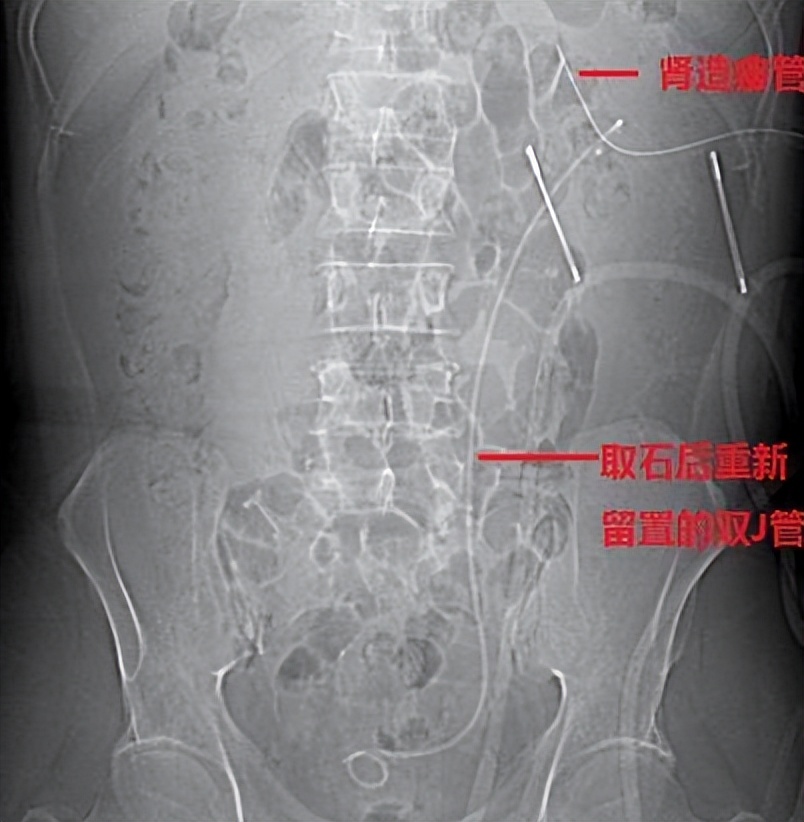

术后的一些处理,就是包括放置D-J管。还有肾造瘘管,术后应用抗生素或相应的止血药物 。如果有残余的结石,可以通到窦道,如果你取出的石头,在5~7天之后可以二期取石。